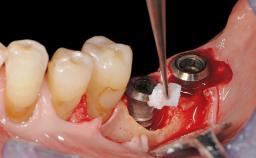

Peri-Implant Mucositis Associated with Misfit of a Cemented Restoration

A 37-year-old male patient was referred to the Department of Periodontology at the University of Bern, Switzerland, by a private dentist. Tooth 21 had been lost due to trauma and had been replaced with an implant and a cemented single crown. The tapered-effect tissue-level implant had a diameter of 4.1 mm, a length of 12 mm, and a sandblasted and acid-etched (SLA) surface (Straumann Dental lmplant System; Institut Straumann AG, Basel, Switzerland). The metal-ceramic crown had been cemented permanently, leaving a submucosal gap between the implant shoulder and the crown margin. Absence of marginal bone loss apical to the polished transmucosal neck of the implant could be observed .